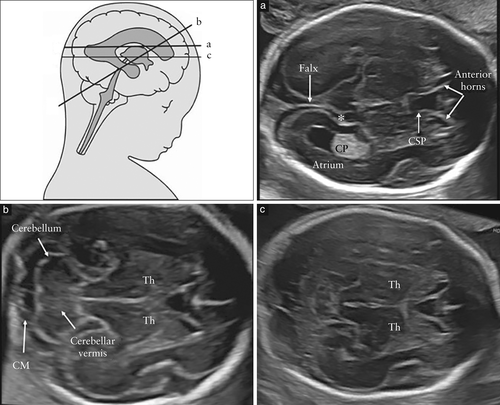

整个妊娠期中,大脑和脊柱的结构都会发生变化。为了避免诊断错误,熟悉不同孕龄的正常中枢神经系统表现非常重要(图1),尽管大多数诊断中枢神经系统异常的临床行为都集中在妊娠中期上。因此,建议在孕中期异常扫查检查期间应用本指南。

图1 整个妊娠期间胎儿大脑的正常形态变化,在横断平面上的超声检查所见:在妊娠第12、21和32周时在经侧脑室、经丘脑和经小脑的平面中观察。请注意,从妊娠中期到妊娠中期,侧脑室和脉络丛的结构发生了显着变化,只有在妊娠中期出现透明隔腔。尽管如此,在妊娠中和晚期,脑室宽度仍保持相对稳定。第1行:经侧脑室平面;第2行:经丘脑平面;第3行:经小脑横切面